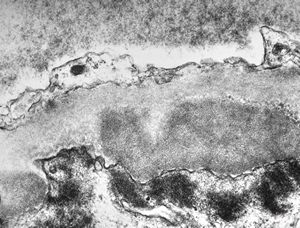

M,22y. | type II membranoproliferative glomerulonephritis